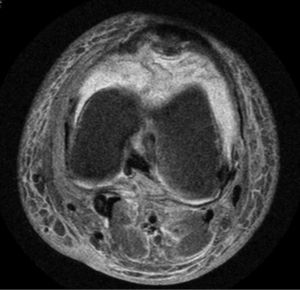

Se realizó una artrocentesis que mostró un líquido hemático (hematíes 940.000μl, células nucleadas 24.550μl —linfocitos 11% y neutrófilos 89%— y proteínas 56g/l). La radiología simple de la rodilla fue normal, y en una RMN se observó abundante derrame articular e importante infiltrado edematoso circunferencial intraarticular, que se describió como compatible con hemartros, sin otros hallazgos patológicos (fig. 1). Por otro lado, también se realizó una biopsia de las lesiones purpúricas cutáneas, que mostró extravasación hemática y siderófagos sin infiltrado inflamatorio.